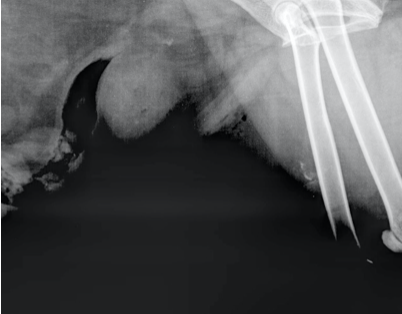

Nommez l’artéfact visible sur cette projection.

A) grille anti-diffusante à l’envers

B) double exposition

C) mauvais alignement de la cassette

D) surexposition

A)